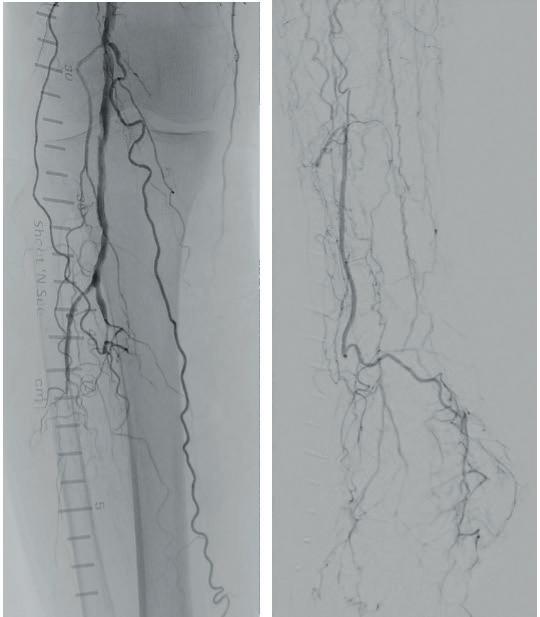

A 75-year-old female patient with diabetes and end-stage kidney disease (ESKD) presented with progressive right second toe swelling ulceration with gangrene and rest pain (Figure 1). There was extensive osteomyelitis and underlying tissue injury which required a planned amputation of the second toe. We were consulted prior to amputation for angiography, which demonstrated patent inflow vessels but severe BTK tibial disease. The baseline angiogram is shown in Figure 2. There was no inline flow to the foot, with occlusion of the anterior tibial, posterior tibial and peroneal arteries (Figure 2a). There was reconstitution of the peroneal artery, with partial filling of the posterior circulation via the posterior communicating artery. There was reconstitution of the anterior circulation with a visible small dorsalis pedis artery (Figure 2b).

Procedural overview

Given the angiosome of the tissue loss, we elected to pursue opening the anterior tibial CTO. Access with a 5F, 70cm sheath was used from a contralateral femoral approach. Using a 0.014” microcatheter and wire escalation, we were able to cross into the true distal lumen of the distal anterior tibial circulation using a 12-gram tipped guidewire (Figure 3a). A 2.5mm Shockwave E8 was used for multiple treatments along the entire length of the CTO segment (Figures 3b, 3c). Post IVL therapy, angiography showed brisk flow through the anterior tibial and into the distal anterior circulation of the foot (Figures 4a-c). This improvement in circulation allowed for this patient to undergo her planned second toe amputation with primary close (Figure 4d).